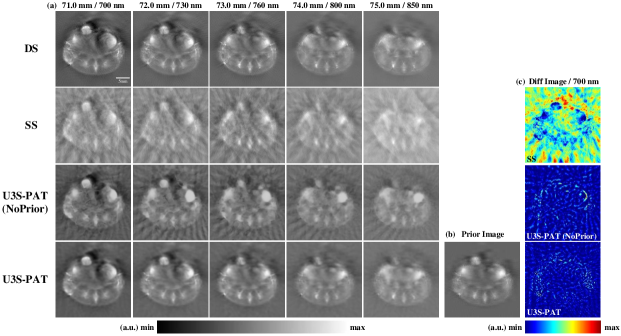

Fig.4 (a) and Fig.5 (a) display the image reconstruction results and the densely sampled (DS) reference images at different slice position and different wavelength. To investigate the impact of prior embedding, we also obtain the reconstruction results of U3S-PAT without the use of the prior image, i.e., random initialization is used during network training. As can be seen, both the sparsely sampled (SS) and U3S-PAT (NoPrior) methods suffer from significant background artifacts at the two transducer settings. In contrast, our U3S-PAT method effectively eliminates these artifacts, yielding reconstructed images of much better quality with well-defined anatomical structures and organ boundaries. When comparing Fig.4 (a) and Fig.5 (a), it could be seen that with even fewer transducer elements, the proposed method still produced acceptable results. In contrast, the image quality of the SS and U3S-PAT (NoPrior) reconstructions degraded heavily as the number of transducer elements decreased.

By comparing U3S-PAT with or without prior embedding, we observe that the introduction of prior significantly enhances image sharpness and reduces artifacts. Notably, despite utilizing the same prior image and relying solely on sparsely sampled data at each stage for image reconstruction, the resulting images accurately capture continuous tissue variations at different slice locations. To further observe the accuracy of the reconstructed images, absolute normalized error images between the reconstructed images obtained using each method and the corresponding reference images are calculated. Fig.4 (c) and Fig.5 (c) display the difference image between the reconstructed image at 21.0 mm / 700 nm and the corresponding DS reference. The U3S-PAT method exhibits the smallest error, emphasizing its superior performance compared to other methods. Moreover, comparing the results obtained from and , the U3S-PAT images vary little with the number of transducer elements, while the absolute difference images of SS and U3S-PAT (NoPrior) became significantly worse as fewer transducer are used.

Next, we perform quantitative evaluation of the image reconstruction results. We use peak signal noise ratio (PSNR) and structural similarity (SSIM) for evaluation, and the obtained results are presented in Table I. At , the U3S-PAT results showed an average increase of 120.48 in PSNR and 34.31 in SSIM compared to the SS results. At ND=16, the PSNR increased by 106.15 and SSIM increased by 39.25 on average. This means that the intensity values obtained by the U3S-PAT method are closer to the reference DS image in both settings. In addition, when and , U3S-PAT improves PSNR by 18.87 and 19.89, and SSIM by 16.70 and 18.30, respectively, compared to the U3S-PAT (NoPrior) method. U3S-PAT method consistently achieves superior performance across all metrics when utilizing prior embedding.

4.2 Spectral unmixing results

Fig.7 shows the image reconstruction and spectral un-mixing results of the in vivo animal experiment with . The images reconstructed by different methods are depicted in Fig.7 (a). Analysis of the images reconstructed using the SS and U3S-PAT (NoPrior) methods reveals the presence of numerous artifacts, attributable to inadequate measurement angle and the absence of prior constraints. In contrast, the images obtained with the U3S-PAT method exhibit cleaner results, closely resembling the DS image. Fig.7 (c) illustrates the distribution images of and , obtained by applying the linear spectral unmixing algorithm to each set of images. The spectral unmixing outcomes highlight the influence of artifacts in the reconstructed images on the unmixing accuracy. The results achieved by the U3S-PAT method align closely with the DS method, enabling clear differentiation of the distributions of and along organ contours.

The quantitative evaluation of the spectral unmixing experimental results is presented in Table II. The results demonstrate that the U3S-PAT method outperforms other methods in terms of PSNR, SSIM, and Dice metrics: compared to the SS method, the PSNR and SSIM increased for 100.50 and 27.00, respectively, and the Hb-Dice and HbO2-Dice increased for 202.39 and 320.59, respectively.